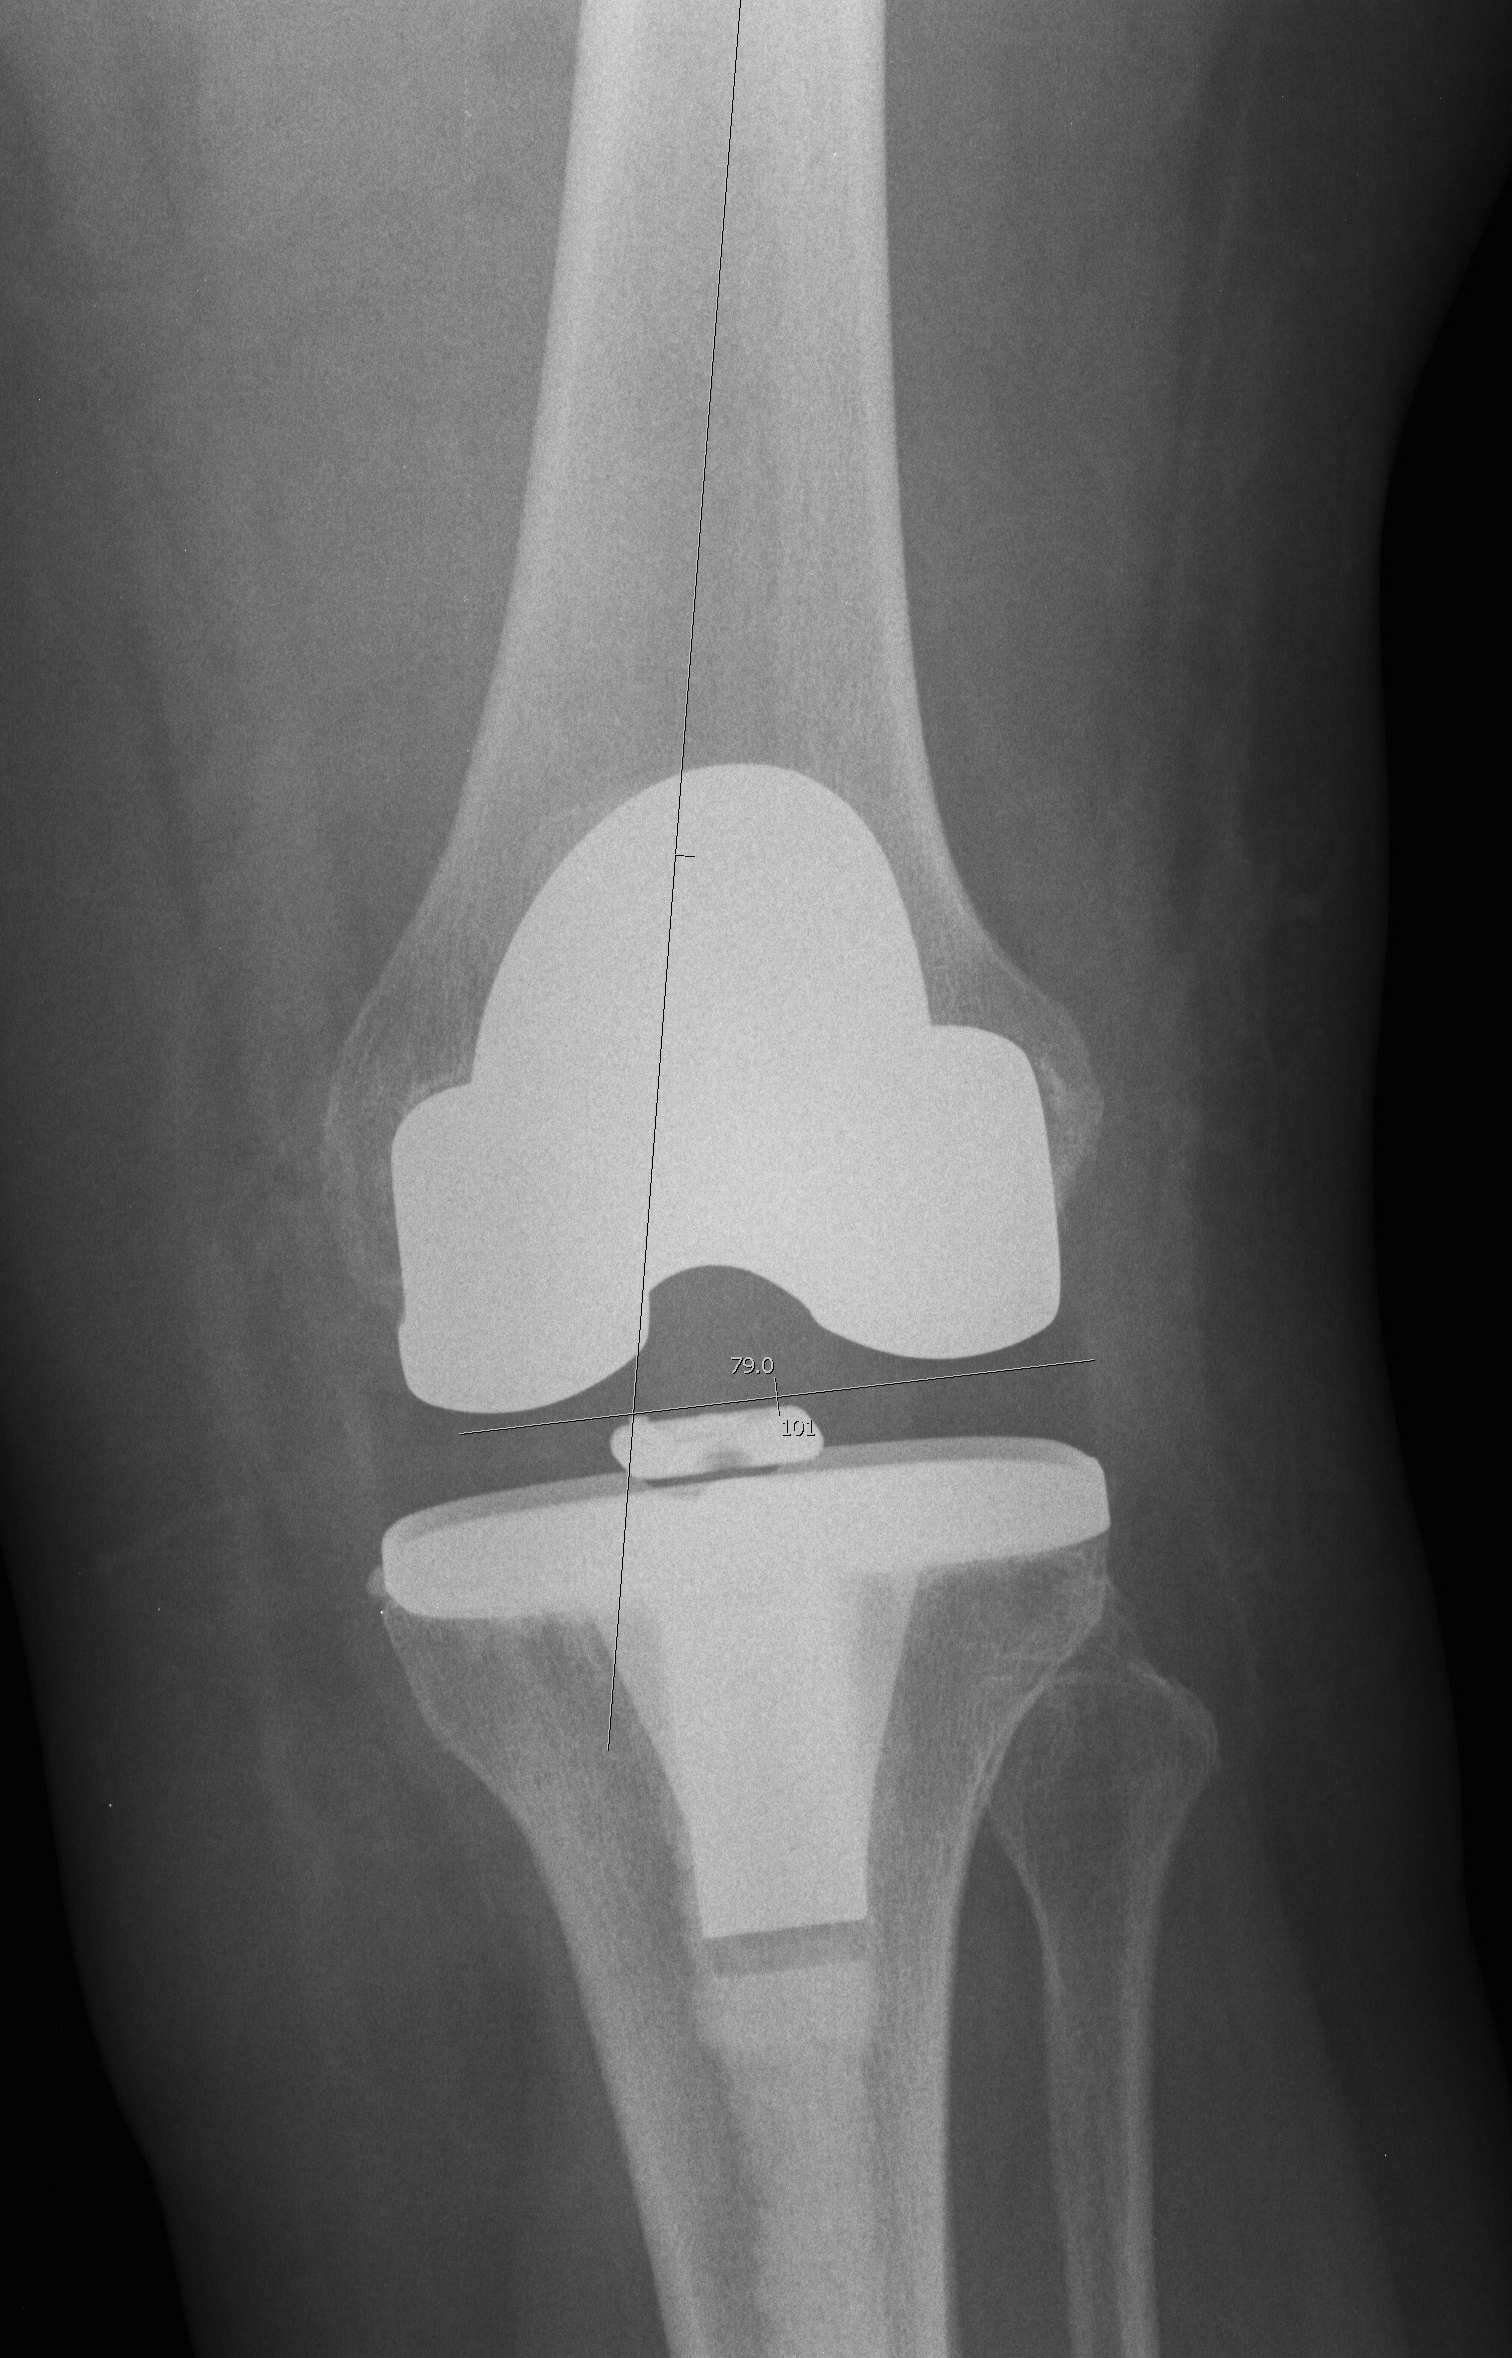

Management Bone Defects

AORI / Andersen Orthopedic Research Institute

T Tibial F Femoral

1. Contained Metaphyseal Defect

2. Damaged Metaphyseal

A. One Condyle

B. Both Condyles

3. Deficient Metaphysis +/- collaterals +/- extensor mechanism